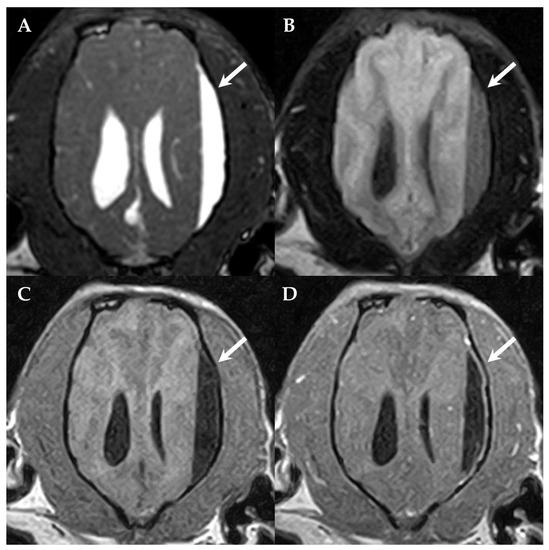

2. Case Presentation